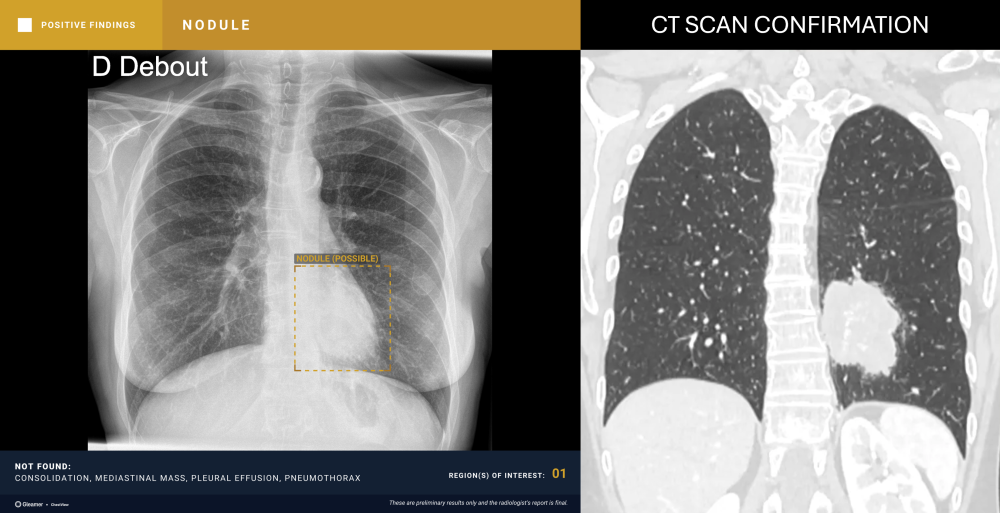

Indication

A 26-year-old male smoker with persistent cough.

Results

ChestView detected a suspicious nodule, confirmed by CT.